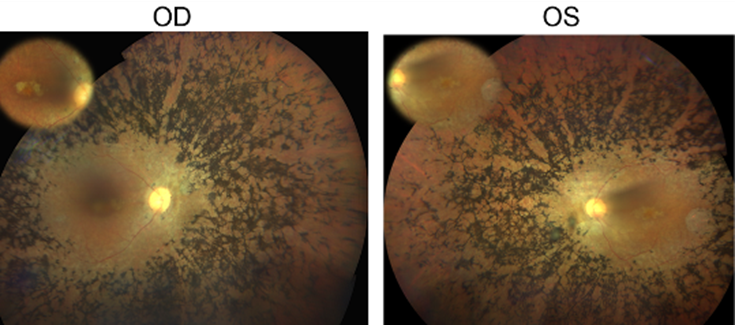

(*) Explicación de la figura: Fondo de ojo del paciente con retinitis pigmentosa en el que se ha identificado la mutación en el gen CFAP20. OD=ojo derecho, OS=ojo izquierdo.

Por último, la estrategia validada se ha aplicado sobre un conjunto de 14 individuos pertenecientes a familias de DHR sin causa genética conocida. Como resultado de ello se ha podido identificar una variante en el nuevo gen candidato CFAP20 (c.337C>T; p.Arg113Trp) que segrega con la enfermedad en una familia consanguínea de RP no sindrómica.

Los estudios de expresión (qPCR) y de localización (inmunohistoquímica) mostraron la presencia de CFAP20 en la retina humana. Aunque variantes en CFAP20 no se han asociado anteriormente con la aparición de ninguna patología en humanos, estudios previos en modelos animales y celulares han demostrado que CFAP20 tiene un papel clave en el funcionamiento y morfogénesis del cilio, apoyando su posible implicación en el desarrollo de ciliopatías humanas, como son algunos tipos de DHR. Por último, se sabe que CFAP20 interactúa con otra proteína ya asociada a la retinosis pigmentaria, ARL2BP.